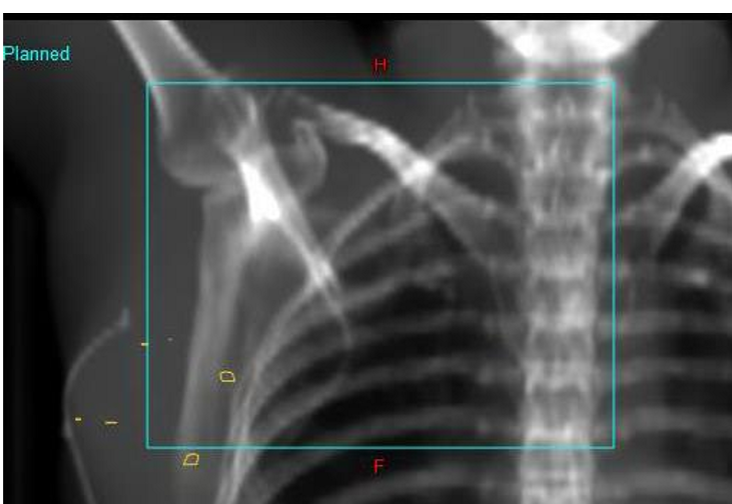

what set of images are done for field localization in breast treatments?

orthogonal reference images: often ANT and LAT images

taken at vertical and horizontal planes

what does the wire define on the x-ray imaging?

wire defines the surgical scar

what are the yellow contours on the image?

contours placed by dosimetry to mark the site of surgical clips

What are the primary and secondary match structures for Sup/Inf for breast treatments

primary = clavicle head - sternoclavicular joint region

secondary = intervertebral spaces, apex of lung, ribs, carina